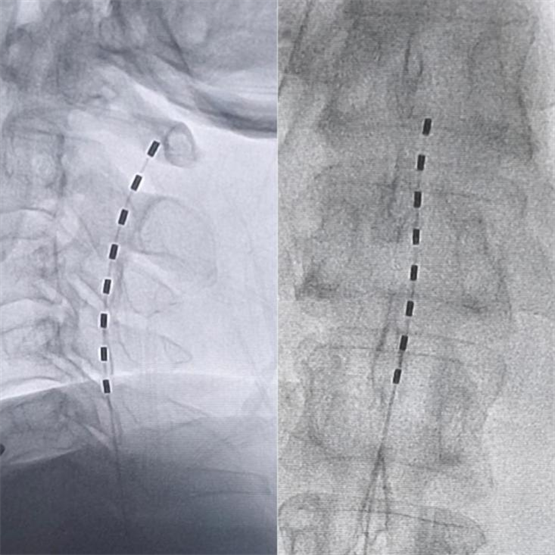

针状电极:微创且同时覆盖上下肢

我们通过精准定位,在脊髓背柱的特定节段放置电极,释放微弱的电流。这个电流可以干扰并“覆盖”原本上传至大脑的剧烈疼痛信号,将其转化为一种轻微的酥麻感。手术中,我们借助电生理监测,精确找到覆盖患者疼痛区域(右侧上下肢)的最佳刺激点,并确保健康侧不会产生异常感觉,避免不适。